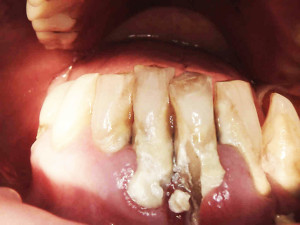

Na drugiej wizycie przeprowadzono dokładną kontrolę pozabiegową. Oznaczono ponownie wszystkie wskaźniki notując znaczną poprawę – API 17%, PBI 33%, sprawdzono głębokość kieszonek i ruchomości zębów.

Płytkę bakteryjną stwierdzono tylko w jednęj przestrzeni, krwawienie w dwóch, niektóre kieszonki spłyciły się. Niestety pani odłożyły się nowe złogi kamienia przy zębach siecznych. Przeprowadzono dokładny instruktaż szczotkowania i nitkowania, dobrano dla pacjentki odpowiednie środki do codziennej higieny jamy ustnej: szczoteczki międzyzębowe , pasty, płukanki, nici oraz skierowano dalej do periodontologa w celu przeprowadzenia dokładnego badania głębokości kieszonek i ewentualnego zabiegu root planingu .